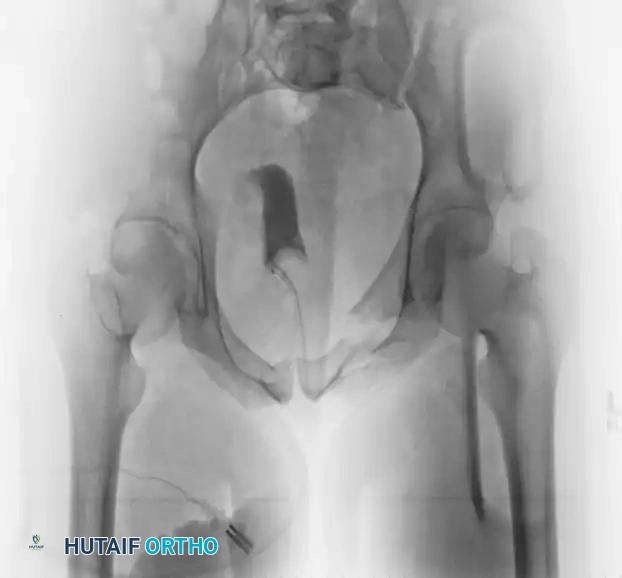

FIGURE 56-43: Young and Burgess anteroposterior type II (AP II) pelvic ring injury with pubic diastasis treated with anterior fixation. A and B, Preoperative views. C-E, Postoperative anteroposterior, inlet, and outlet views.

The preoperative AP view demonstrates significant widening of the symphysis pubis.

Postoperative AP, inlet, and outlet views confirm anatomic reduction of the anterior ring and restoration of pelvic volume.